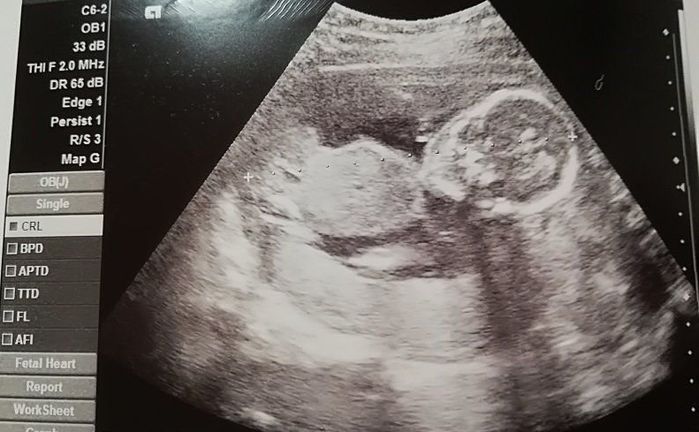

妊娠18週目のエコー写真

頭がくっきり。そして足を曲げている様子もわかります。5カ月目に入り、ようやくつわりがおさまりました。早速、やりたかったマタニティーヨガに挑戦。結果は、お香の匂いと逆転のポーズで吐いてしまいました。ちょっと調子に乗りすぎたようです。でも、ちょうど紅葉の季節にさしかかり、一泊旅行に出かけるなど楽しいことがたくさんできました。